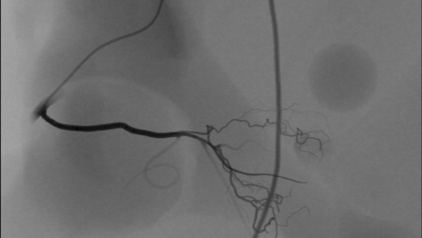

This module aims to enhance technical and procedural skills for the challenging Prostatic Artery Embolization technique, used to treat benign prostatic hyperplasia. The embolization is performed by injecting spherical and non-spherical particles of various sizes.

- Become proficient in prostatic artery embolization techniques (PerFecTED and standard)

- Learn to evaluate prostatic artery occlusion using fluoroscopy and Cone Beam Computed Tomography (CBCT)